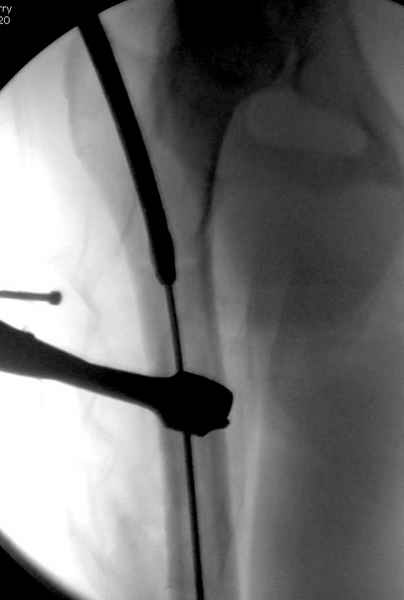

Второй случай тоже репозиция из малого доступа, больному 19 лет, множественные огнестрельные повреждениия конечностей, живота и черепа, правая конечность холодная, без пульсации. Ортопедический диагноз: огнестрельный перелом правого бедра. При срочной ангиографии повреждения сосудов не подтвердилось, конечность из-за ургентности состояния больного зафиксирована временным наружным фиксатором и больной оставлен на операционном столе для срочной лапаротомии хирургической службой.

Больной долго оставался нестабильным, только на 14 день удалось заменить на антеградный интромедуллярный штифт TFN (trochanteric femoral nail) SmithNephew. После неудачной попытки закрытой репозиции, несмотря на использование "joystick", проксимальный стержень от

наружного фиксатора, (перелом начал срастаться) репозицию провели из малого доступа, затем остальные этапы операции.

Случай был представлен из-за того, что больного оперировали после наружной фиксации и был риск инфекцирования через места проведения стержней (на снимках), прошло больше 3 месяцев, выписан из амбулаторной службы из-за отсутсвия надобности дальнейшего наблюдения.